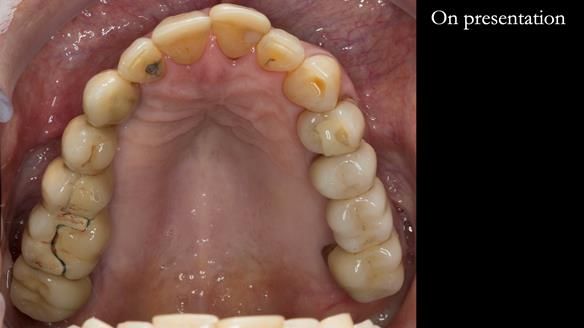

The starting point

We began with the lower jaw.

A posterior implant 47 had lost integration and was infected. This was removed.

Ken did not want further implant surgery.

Instead, we made a Scandinavian-style, metal-based lower RPD.

The upper jaw

In the upper arch:

- a failing upper left tooth supporting a bridge was removed

- an implant-supported bridge on the upper right was dismantled

A metal-based upper RPD was made,

with metal backings incorporated to future-proof the design

should further teeth fail.

This case was always about function, not aesthetics.

Ken’s teeth were never going to look perfect.

There were stained composites, old restorations, and obvious wear.

That was accepted from the outset.

The way Rowan lengthened the teeth — particularly in the upper RPD — to match the existing gingival recession on the remaining teeth was superb. The dentures sit naturally within the context of the rest of the mouth.